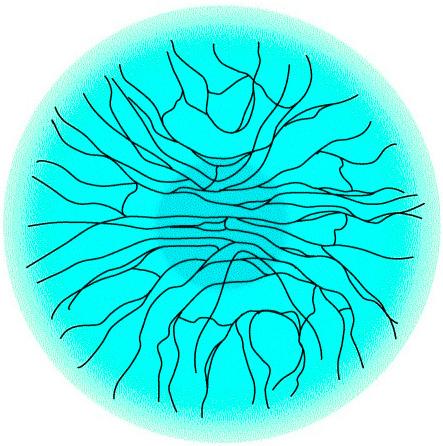

Plesso nervoso corneale Fasci stromali, distribuzione radiale

La compromissione dell’omeostasi della superficie oculare può talvolta originare dalla parziale resezione del plesso nervoso che può portare ad uno stato di occhio secco per deficit neurotrofico. Si ricordi infatti che la cornea è un tessuto avascolare e che dipende dai nervi sensoriali per il supporto trofico, sappiamo come nel caso della chirurgia refrattiva il plesso nervoso viene modificato, durante l’esecuzione del lembo corneale; l’integrità nervosa è preservata solo nel punto della cerniera (come nel caso della LASIK). Un ulteriore danno in profondità, nello stroma corneale, è proporzionale all’entità dell’ablazione e cioè del difetto da correggere. Un ruolo negativo inoltre nella LASIK può essere associato all’anello di suzione che, a causa della pressione esercitata, può danneggiare le cellule globose mucipare della congiuntiva ed i microvilli.

Incisione a tre step

con le moderne tecniche “microincisionali”, dove possono essere inferiori anche a 2 mm, interrompono lo stesso il percorso radiale dei nervi creando cosi l’area di perdita della sensibilità corneale. Il danno al plesso nervoso comporta in ogni caso una minor sensibilità corneale, un ridotto ammiccamento, con un’aumentata evaporazione del film lacrimale e con un attenuato stimolo alla sua produzione. Questa perdita può richiedere mesi per tornare allo stato iniziale mantenendo così alterata l’omeostasi per tutto il tempo fino alla sua risoluzione.